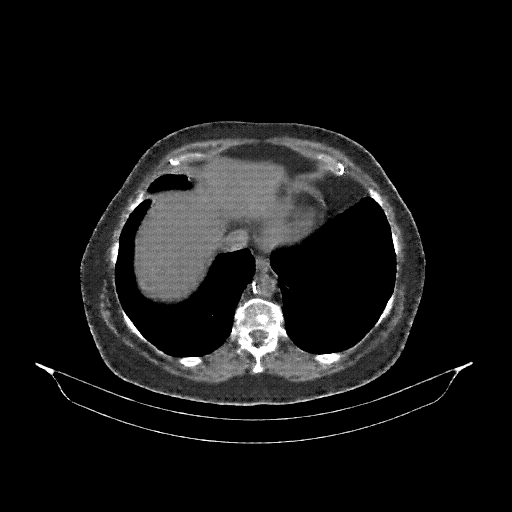

Image Grid

4Γ—3 grid: Rows show different image types (Original NATIVE, Reconstructed NATIVE, Original VENOUS, Generated VENOUS), Columns show windowing techniques (No Window, Lung Window, Mediastinum Window)

Mediastinum window (WL 40, WW 400 β†’ Low βˆ’160, High +240)